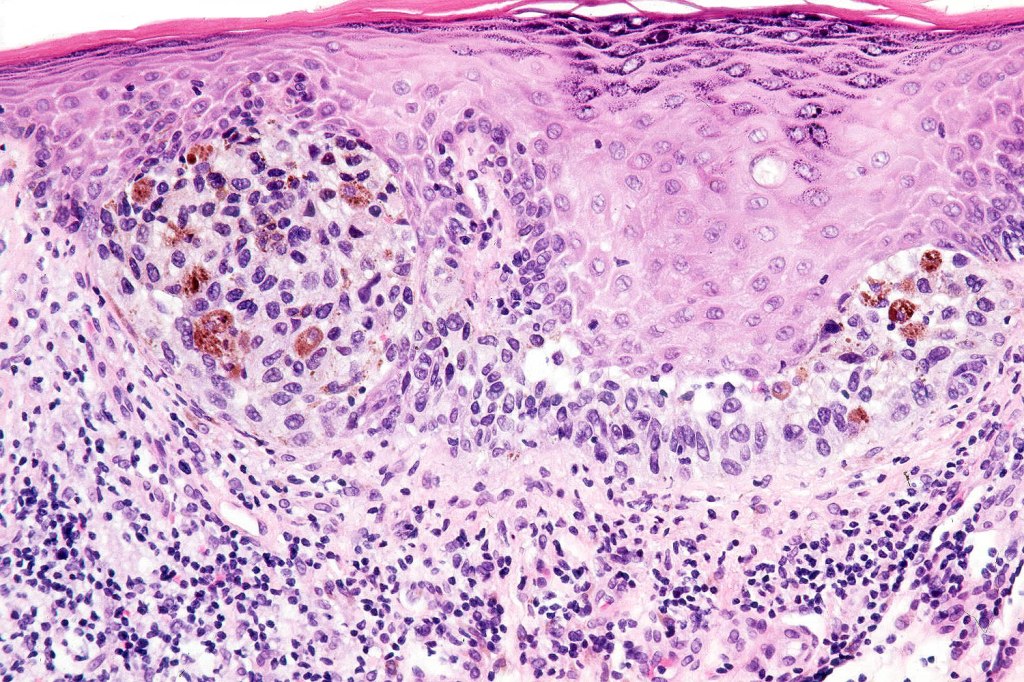

Histological features

•Junctional/compound

•Large dyscohesive nests with retraction artifact, not restricted to the tips of the epidermal ridges

•Heavy pigmentation (sometimes gray/green)

•Bridging common, often over multiple rete ridges

•Variable atypia (can be marked)

•Central pagetoid spread

•Superficial dermal atypia

•Junctional mitoses sometimes present, dermal mitoses+/-, can be multiple but never atypical

•Dermal fibrosis (sometimes lamellar)